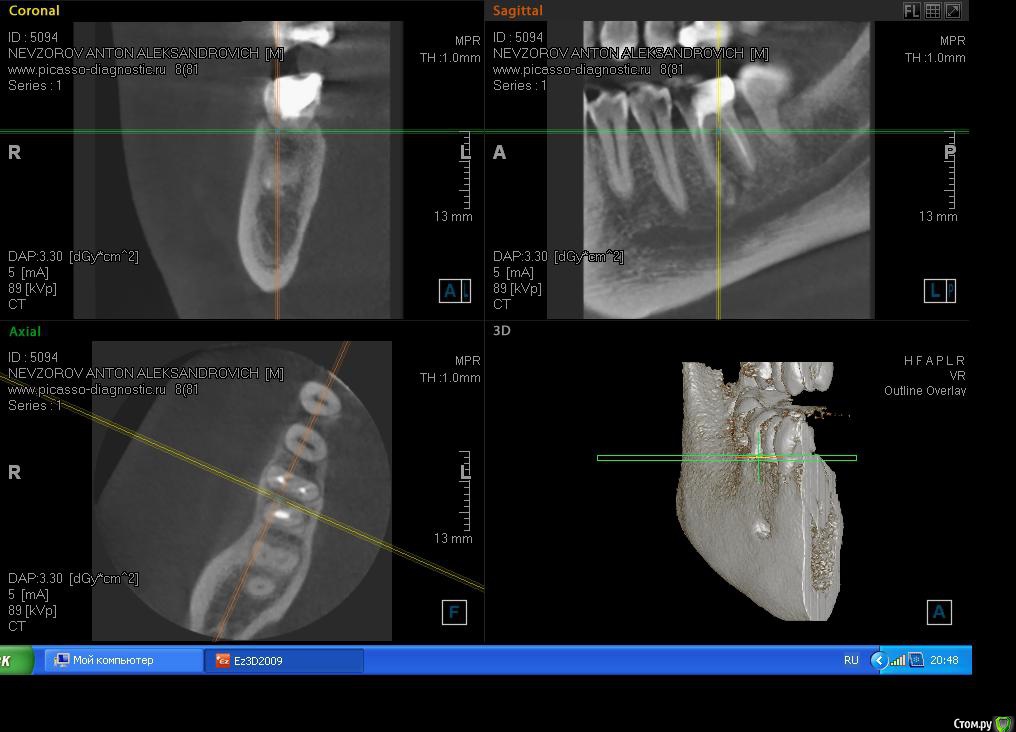

Antonbet Опубликовано 30 апреля, 2015 Поделиться Опубликовано 30 апреля, 2015 Подскажите,мнение врачей разделилисьОбнаружилась киста на 6 зубескажите что делать пролечивать каналы заново(4-5 мес.за 10 000 руб.) затем ставить коронку (15000 руб.) или удалять зуб и ставить имплант с коронкой (30 000 руб.),пр-во Израильесли имплант то можно ли ставить израиль ? или только швейцарию,Сша,они в 2 раза дорожеспасибо Ссылка на комментарий

Чертков Александр Опубликовано 30 апреля, 2015 Поделиться Опубликовано 30 апреля, 2015 Я за "перелечить". Судя по данным томограммы - вполне "жизнеспособный" зуб. План разумный. Ссылка на комментарий

Yana guapa Опубликовано 30 апреля, 2015 Поделиться Опубликовано 30 апреля, 2015 Подскажите,мнение врачей разделилисьОбнаружилась киста на 6 зубескажите что делать пролечивать каналы заново(4-5 мес.за 10 000 руб.) затем ставить коронку (15000 руб.) или удалять зуб и ставить имплант с коронкой (30 000 руб.),пр-во Израильесли имплант то можно ли ставить израиль ? или только швейцарию,Сша,они в 2 раза дороже спасибоImage.jpgImage1.jpg и первый и второй вариант лечения имеет право быть. Для первого варианта надо найти хорошего терапевта, желательно работающего с микроскопом. Но гарантий после перелечивания , конечно, немного все равно. Ну а по стоимости даже по нашим провинциальным меркам это ооочень не дорого, хорошее перелечивание каналов с микроскопом стоит дороже, да и импланты сейчас подросли в цене. Ссылка на комментарий